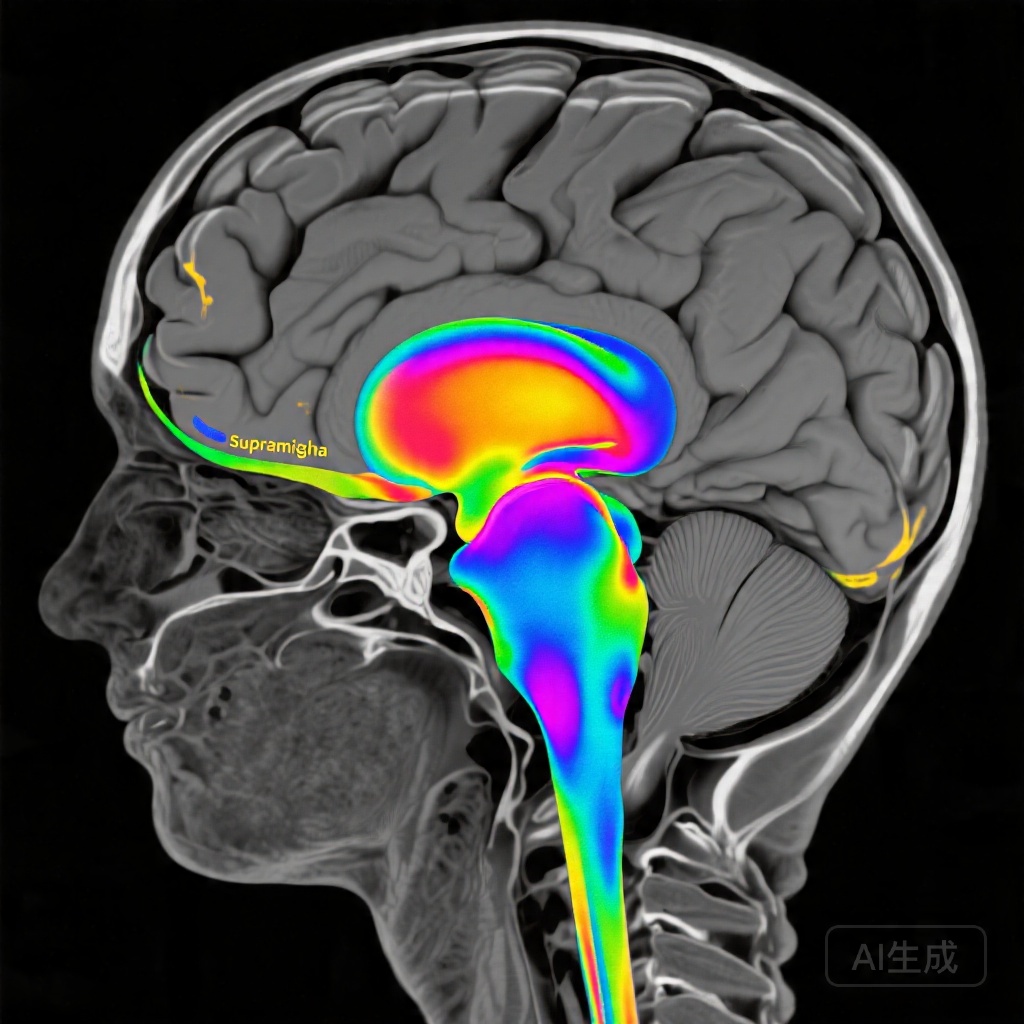

The emergence of real-time fMRI neurofeedback offers a promising neuromodulation strategy that enables patients to visualize and consciously modulate their own brain activity in specific regions implicated in language function. Unlike transcranial magnetic stimulation or transcranial direct current stimulation, fMRI neurofeedback provides direct hemodynamic-based feedback from the target region, potentially allowing for more precise targeting of task-specific neural circuits. The left supramarginal gyrus, a critical hub within the dorsal language pathway, plays an essential role in phonological processing and grapheme-to-phoneme conversion—skills fundamental to reading accuracy, particularly for novel or nonword stimuli.

Analysis of task-based functional imaging revealed striking differences in training-related activation patterns between the contingent and noncontingent neurofeedback groups. The contingent neurofeedback stroke group demonstrated significant activation increases localized to the left supramarginal gyrus during the postintervention scanning session (z=4.7; cluster-family-wise error corrected P=0.05), with expansion of activation within the broader reading network, particularly evident during nonword reading trials. This localization to a reading-specific region during phonologically demanding tasks suggests that the neurofeedback successfully reinforced activity within the intended target region during behaviorally relevant processing.

In contrast, activation increases in the noncontingent stroke group and healthy controls were more widespread and less reading-specific in their topography. Healthy controls showed engagement of additional executive and attentional control regions, potentially reflecting the greater cognitive demands of volitionally modulating an intact neural system, while the noncontingent stroke group demonstrated more diffuse patterns that may represent compensatory recruitment of alternative pathways without the specificity conferred by contingent feedback.